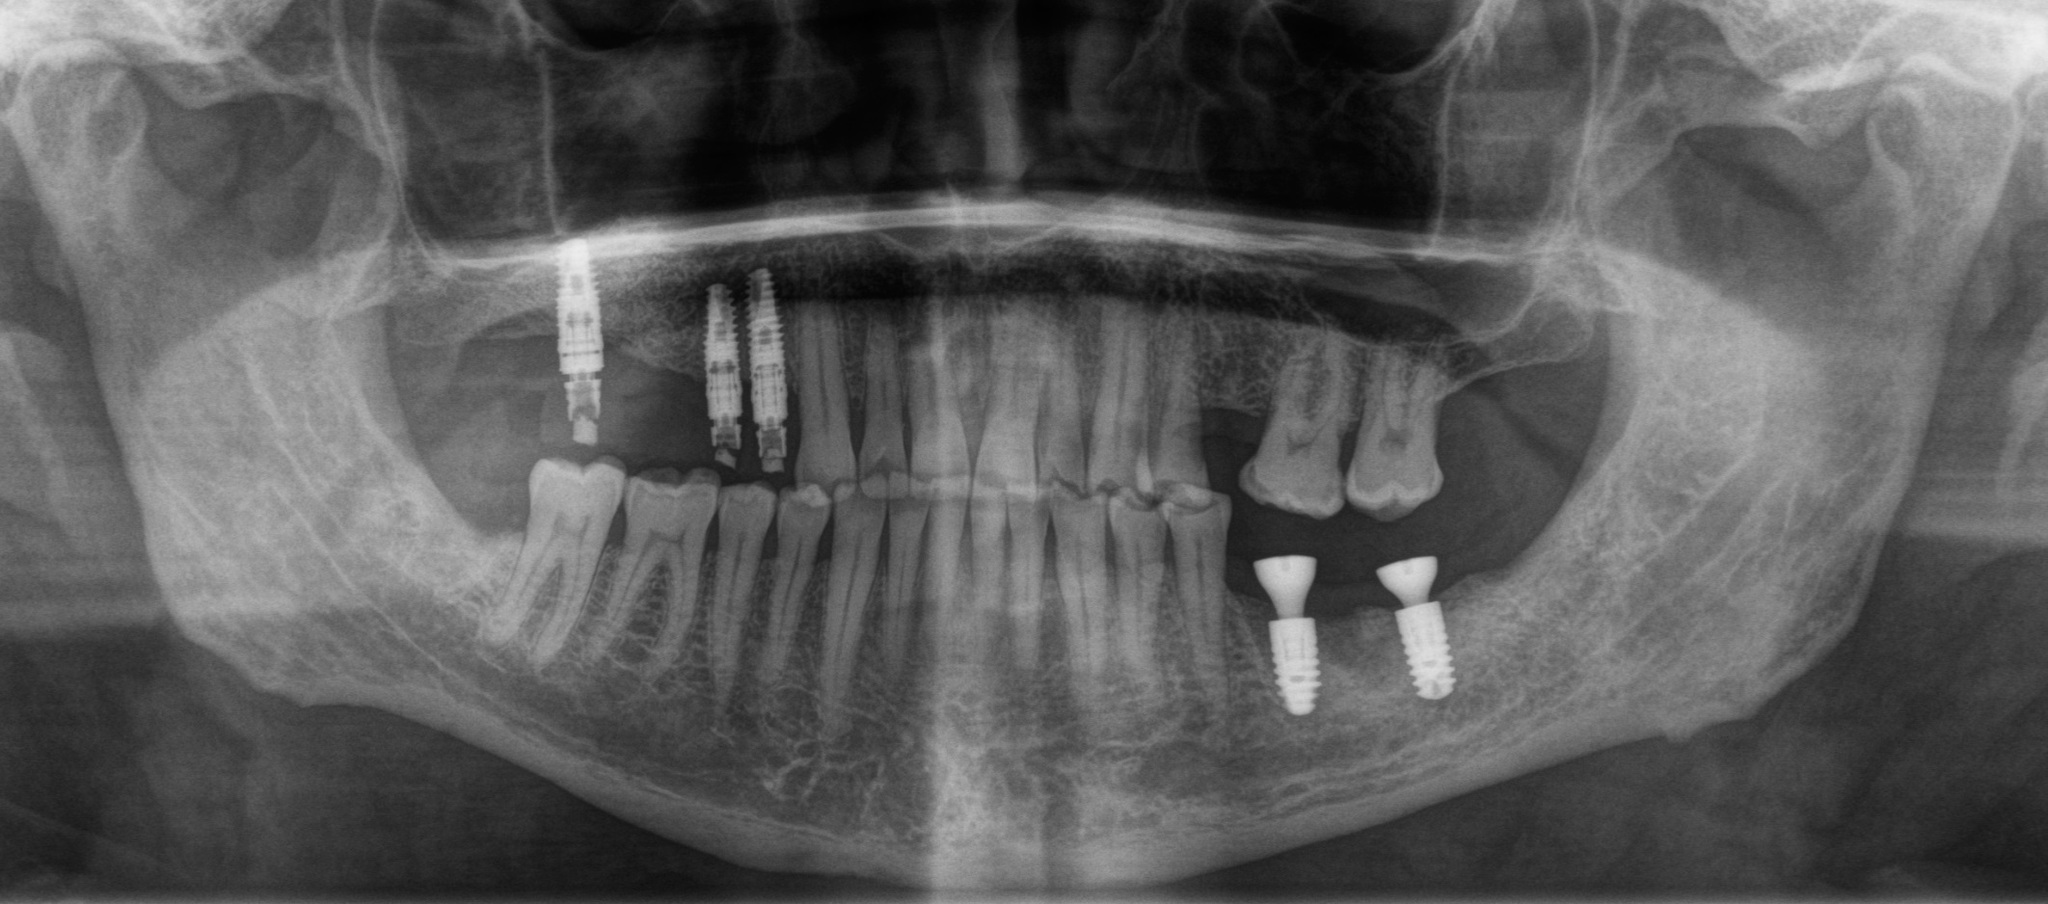

Я искренне надеялся, что это раскрутился винт, фиксирующий коронку к имплантату, но все оказалось куда прозаичнее. Так же, как и в предыдущей статье, причиной был перелом винта:

Рентгеновский снимок после извлечения винта и снятия мостовидно протеза:

Временным (!) решением данной проблемы была замена фиксирующего винта на новый и фиксация этого же мостовидного протеза на место:

Было принято решение об удалении зуба и установке имплантатов в области 5 и 6 зубов:

Январь 2024. Наши дни. Установка постоянных безметалловых коронок слева сверху: